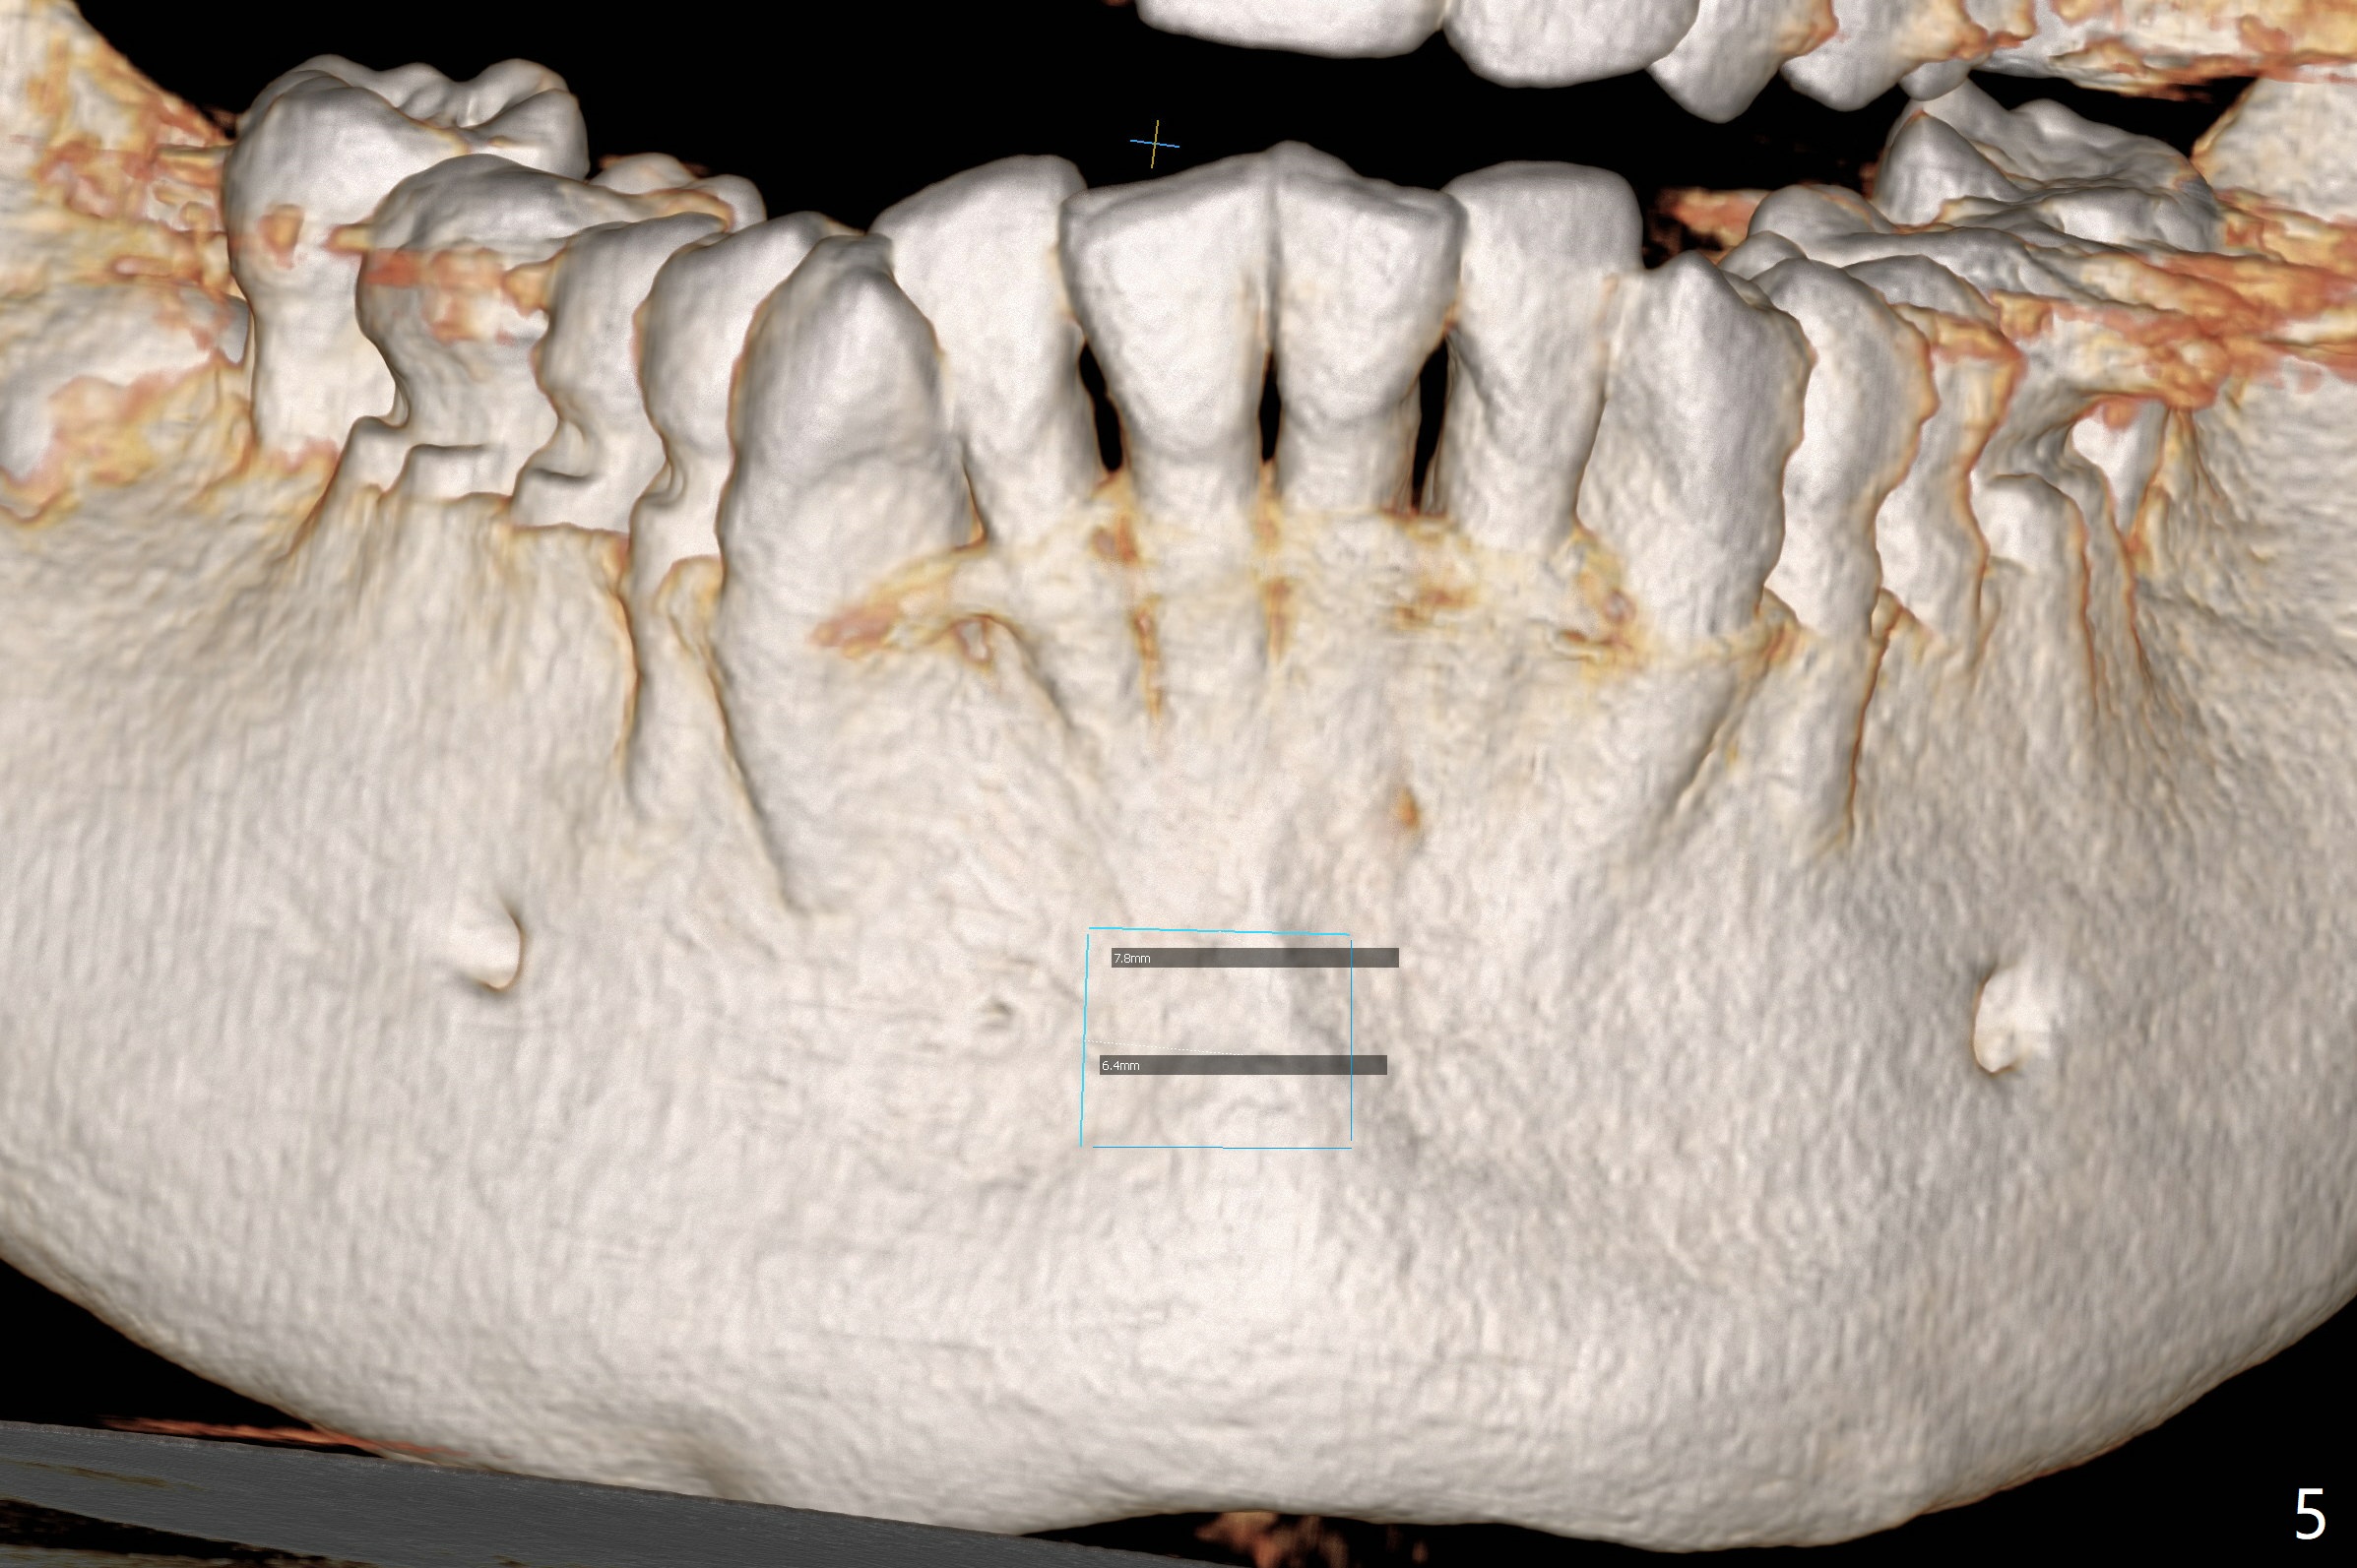

A 51-year-old woman lost the teeth #6 and 7 due to odontoma removal ~30 years ago. The area was restored with a FPD. The latter is removed with immediate implant at #8 8-9 months earlier. Particulate bone graft does not repair the bone deficiency at #6, 7 (Fig.2,3), although the soft tissue looks bulky (Fig.1). It appears that the palatal defect also needs a piece of bone block to fill in (Fig.4). The block will be harvested from the chin (Fig.5,6). If the block graft turns out to be impracticable, the periodontally compromised tooth #5 (bone loss, Fig.2,3,7) will be extracted for immediate implant. Initial osteotomy will be established in the palatal socket (Fig.8,9). Either a 2- (Fig.10) or 1- (Fig.11) piece implant will be placed. After wound healing, impression will be taken for a lab-fabricated provisional FPD.